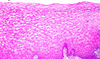

Stratified squamous, non-keratinized